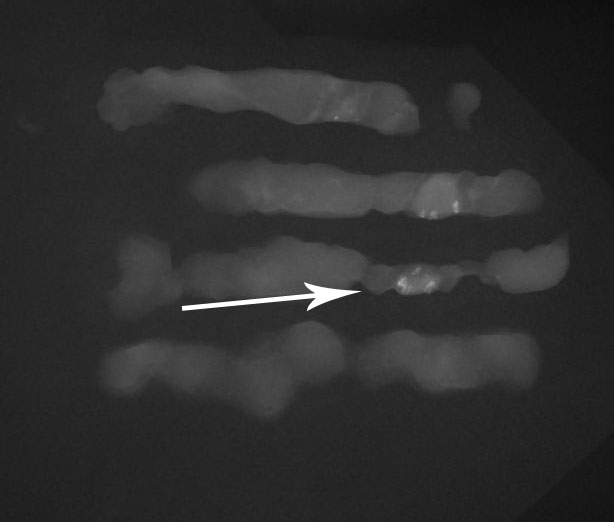

Contrôle radiologique de micro-calcifications dans les prélèvements réalisés par macrobiopsies sous stéréotaxie

Les prélèvements sont alors transmis après vérification à un laboratoire d’anatomo-pathologie pour analyse histologique.